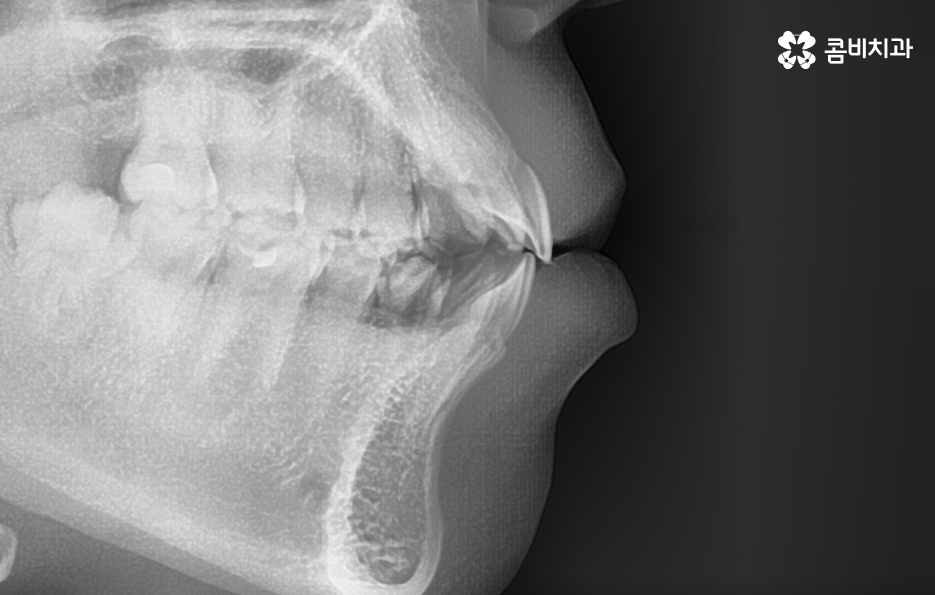

출처 아카이브 열기치아교정의 목적은 다양하지만 돌출입을 개선하고자 하는 목적성을 갖는 경우 발치가 필요한 경우가 대부분이라고 할 수 있는데요. 그 이유는 입이 나와 있는 돌출입을 개선하기 위해서는 앞니 부분이 뒤 쪽으로 들어가야 돌출입이 개선되기 때문인데 치아를 안쪽으로 이동시키기 위한 공간 확보를 위해 발치가 필요한 경우가 많은 거예요.

돌출입을 개선하기 위한 교정 치료의 사례에도 돌출입발치교정 사례가 많은 이유도 치아의 발치를 통해 앞니를 후방 이동시키는 치아 교정의 원리가 있기 때문이라고 설명할 수 있어요

돌출입에 대한 고민으로 치아교정을 고민하신다면 치아교정 후 결과에 있어서 얼굴 변화에 대한 부분이 더 중요하게 느껴질 수 있어요. 치아교정을 통해서 얼굴은 변화할 수 있기 때문에 교정 전에도 3D CT나 모르페우스 등과 같은 장비로 3D 예측을 활용하고 있는데요

보통 치아교정을 통해 눈에 띄게 얼굴 변화를 느끼게 되는 경우는 쉽게 말해 발치를 통한 교정으로 볼 수 있어요. 그 이유는 치아를 발치하게 되면 발치한 만큼의 공간이 악궁에서 축소가 되기 때문에 그로 인해 얼굴라인이 갸름하게 변하게 되거나 돌출입발치교정 같이 돌출입의 개선이 되는 거예요